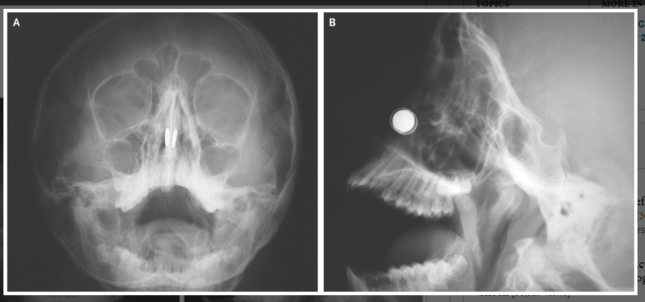

鼻の穴の両側でボタン型磁石(白色の円形)がくっ付いたレントゲン写真。Aは正面、Bは側面(「The New England Journal of Medicine」の論文より)

同誌の論文要約によると、症例を報告したのはキプロスの首都ニコシアの医師、カディフ・カズキダス氏とモハメド・ディリク氏の2人。11歳の少年が顔に猛烈な痛みを訴えて、病院の救急センターに搬送された。顔のレントゲン写真を撮ると、2個の丸いボタン型の磁石が鼻の両方の穴に入っており、鼻中隔(左右の穴を隔てる部分)をはさみ、互いに引き合ってピッタリくっ付いていた(=写真参照)。磁石は、搬送される6時間前に少年が自分で鼻の中に入れた。